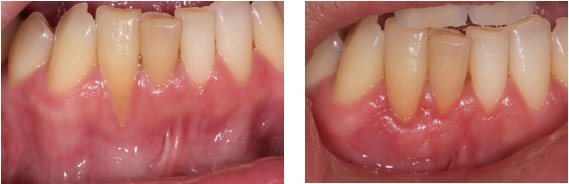

About Michael Wasemiller, DDS Creating Healthy Smiles One Patient at a Time. Dr. Wasemiller specializes in dental implants and periodontal procedures along with advanced minimally invasive sinus lift techniques. Periodontics is the field of dentistry that focuses on the area surrounding the teeth: the bone and gums. Your referring dentist focuses on the restoration of your teeth. Dr. Wasemiller works closely with your referring dentist... (Show more)